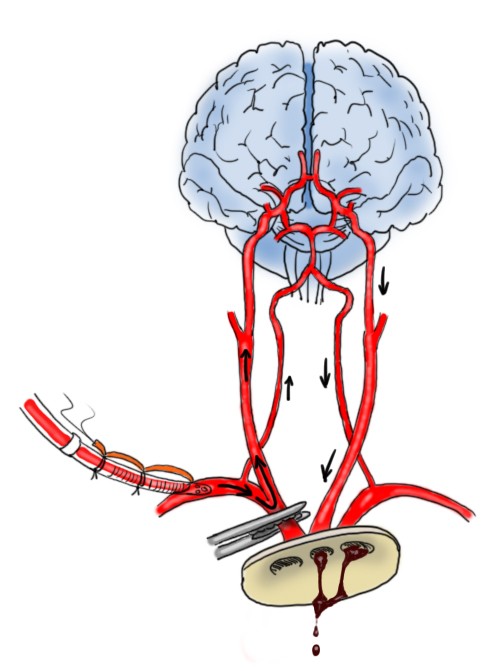

Storicamente, il primo tipo di perfusione cerebrale è stata la perfusione cerebrale retrograda (immagine sopra). In questa procedura, durante l’arresto cardiocircolatorio ipotermico viene inserita una cannula arteriosa nella vena cava superiore. Si imposta quindi un flusso tale da portare la pressione venosa intorno ai 20-25mmHg, sufficienti per invertire il flusso cerebrale (vena cava superiore → seni venosi → microcircolo → arterie). Questa tecnica è semplice ma ha una serie di difetti: non consente tempi di arresto prolungati, la distribuzione del flusso non è omogenea, la perfusione metabolica non è ottimale e vi è rischio di edema cerebrale. Nel corso degli anni è stata superata dalla perfusione cerebrale anterograda.